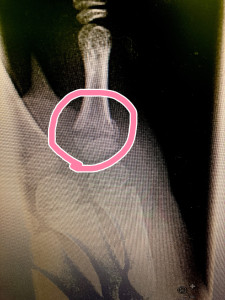

どうしたのか聞くと、学童保育でドッヂボールしていて突き指したとのこと。

湿布やら包帯やら巻かれているので、外して患部を見てみると‥

一目見て、骨折とわかるほどの腫れ😩

後日、固定してレントゲン🩻。

ばっちり折れてました😅